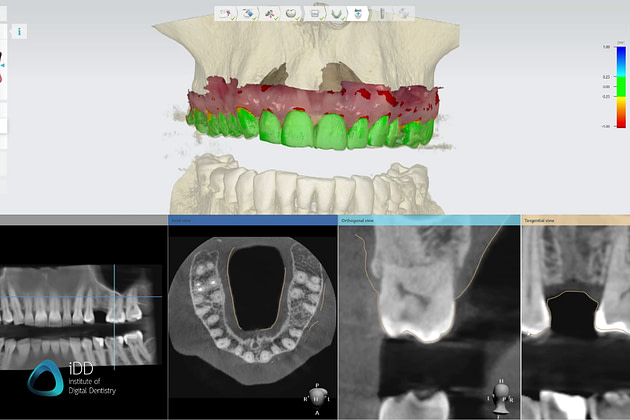

Cone beam CT imaging offers incredibly detailed 3D scans for improved diagnostic abilities and surgical planning.

From subtle caries lesions and periapical pathologies to intricate anatomical landmarks and restorative assessments, mastering this critical skill enables you to paint a comprehensive clinical picture.

With precise radiographic analysis, you can confidently diagnose conditions, formulate qualified treatment plans, and monitor the progression of therapies with greater accuracy.

Accurately identify pathologies, developmental anomalies, and anatomical landmarks on radiographs - bitewings, PAs, and OPGs.